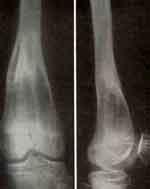

У Игоря Д., 9 лет, метафизарный дефект бедра замещен нами тонкими кортикальными лиофилизировапными гомотрансплантатами по типу «вязанки хвороста» с полным восстановлением структуры кости. В течение 13 лет после операции мальчик совершенно здоров, имеет полный объем движений в коленном суставе, произошла полная перестройка гомотрансплантатов.

Хондросаркома бедренной кости

Хондросаркома бедренной кости у больного 9 лет: до лечения и после резекции и костной пластики лиофилизированными гомотрансплантатами по методу «вязанки хвороста» и результат через 13 лет.